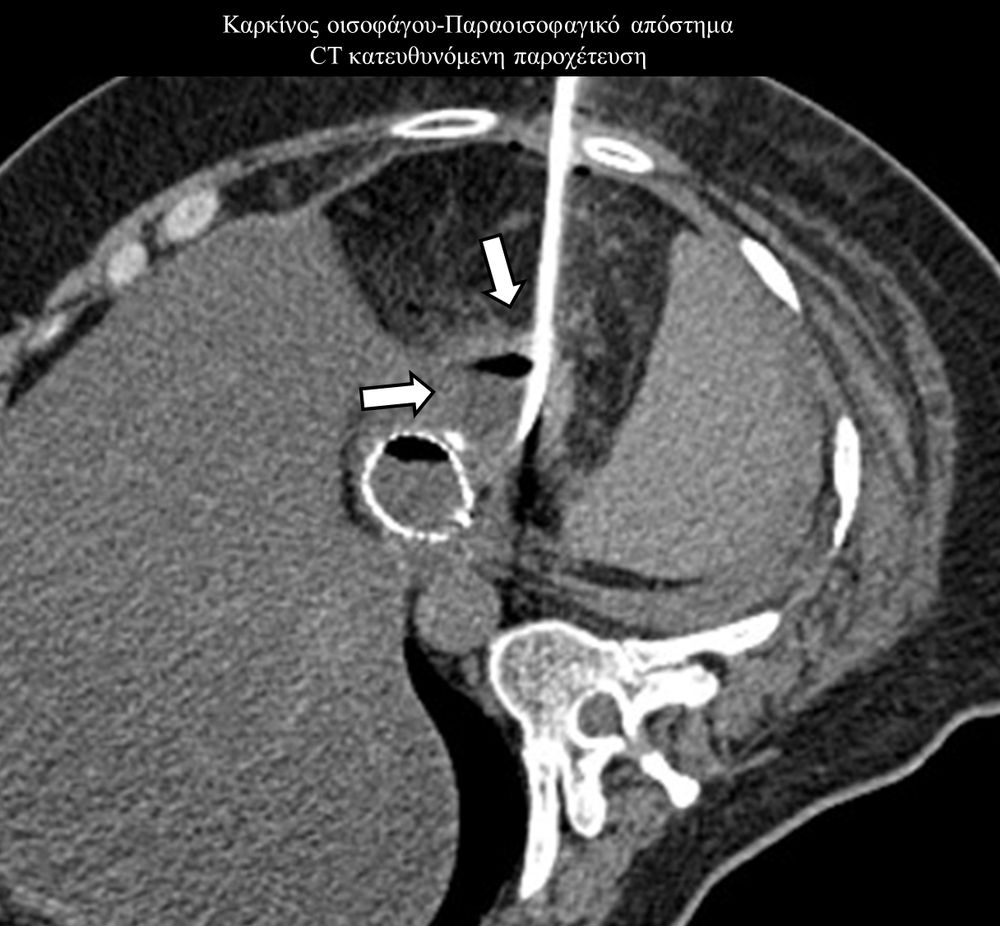

Η παρέμβαση διενεργείται υπό την καθοδήγηση αξονικού τομογράφου ή υπερήχων ή και με συνδυασμό τους. Ο επεμβατικός ακτινολόγος αρχικά αναισθητοποιεί την ανατομική περιοχή ενδιαφέροντος με τη χρήση τοπικής αναισθησίας και παρακεντεί την συλλογή διαδερμικά με λεπτή βελόνη. Στη συνέχεια μέσω ομοαξονικών συστημάτων συρμάτων-καθετήρων-διαστολέωντοποθετείται διαδερμικός καθετήρας τύπου pig-tail εντός της συλλογής, ο οποίος συνδέεται με εξωτερική παροχέτευση.